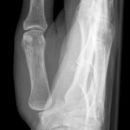

Finger lateral (D II –V) 2.Ebene

Indikation

Frakturen, Luxation

Lagerung

sitzend - seitlich zum Tisch

zu untersuchender Finger streng seitlich

parallel zum Bildempfänger

Zentralstrahl

senkrecht auf Objektmitte

Einblendung

einschließlich Grundgelenk

Anmerkung

D II-III Strahlengang ulnoradial

D IV-V Strahlengang radioulnar

Qualitätskriterien

Vollständige Abbildung des Fingers vom Grundgelenk bis zur Fingerkuppe mit überlagerungsfreiem Einblick in die Fingergelenke. Auf den Seitenaufnahmen kommen ulnare und laterale Kondylen zur Deckung, Einblick in die Fingergrundgelenke D4-D5 gelingt aus anatomischen Gründen meist nicht.